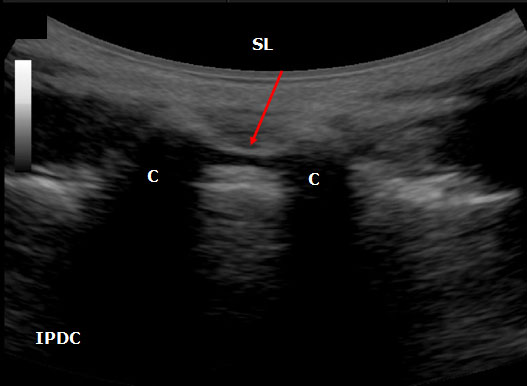

In the transverse approach the transducer is placed perpendicular to the long axis of the spine. The window is identified in which shadow of the spinous processes is minimal. Structures that can be visualized with ultrasound include the ligamentum flavum/posterior dura complex, spinous processes, transverse processes, superior articular processes, facet joints, and the posterior border of the vertebral body. In certain cases it is not always possible to distinguish the ligamentum flavum from the posterior dura and the anterior dura from the posterior longitudinal ligament and the vertebral body. Ultrasound has also been utilized as an adjuvant tool in the performance of caudal epidurals (Figure 16).

Figure 16. An ultrasound image of the sacral hiatus between the sacral cornuae (C) The sacral hiatus is covered by sacrococcygeal ligament (SL) and its depth is defined the base of the sacrum.